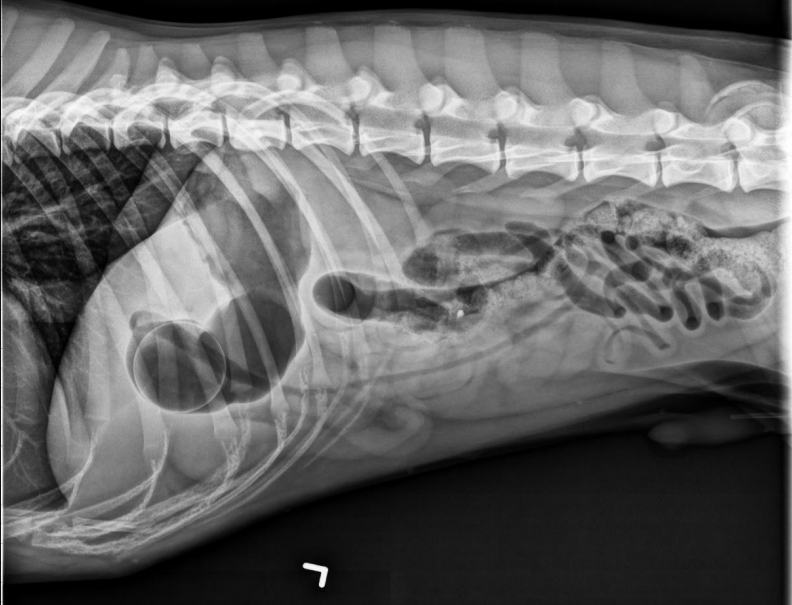

15 yo cat

Weight loss, anorexia, vomiting

Findings:

● Dilated bowel filled with fecal mass

– Not only large intestine, but small

intestine as well.

● Megacolon